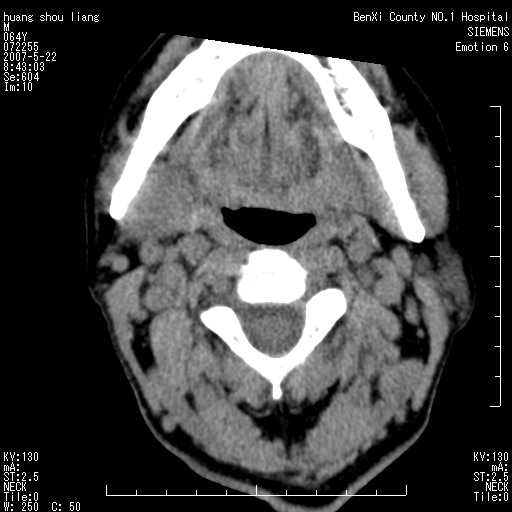

男性,64岁。颈部包块8年。最近增大。

对不起大家,可能是片子发太多有点乱,正常腮腺在下颌角的外侧,颌下腺在下颌体的中部内侧,本例在下颌角内侧偏下,和腺体一点关系都没有,从vrt和mpr上可以很明显看出来,再者肿块是好多粘连在一块的,大家在仔细看看,左侧可能也是吧,我还是考虑为肿大的淋巴结融合在一块,但性质??????

右侧腮腺下部均匀软组织密度肿块,外形不规则,与周围组织分界清晰,考虑右侧腮腺混合瘤或多形性腺瘤。

大家好,病理结果出来了,如大家所说,颌下腺混合瘤。

唉,解剖没学好吧,我诊断错了,不过还是有些不理解回去我在多看看书,谢谢大家的参与,以后我还会奉献好的病例。